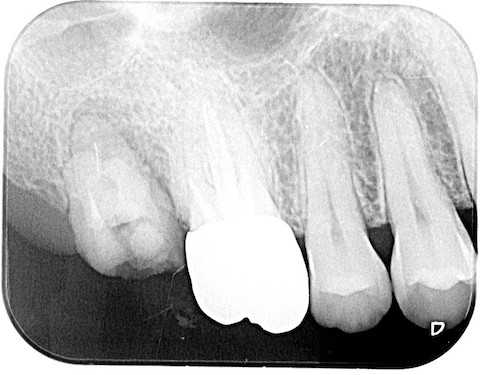

40代女性、左上5、冷水痛+この時のつづきで、術後の冷水痛が完全には治らないということだったので、画像を解析してみた。そもそも冷水痛とは何か?ということだが、歯髄に軽い炎症があるということだ。知覚過敏症という歯が沁みる病態がある。これは象牙質が露出しているのが原因とされているが、露出しているだけでは知覚過敏症にはならない。加えて歯髄の炎症が必要になる。その軽い炎症の原因は虫歯やクラック、修復物の隙間から細菌や電解質の侵入、咬合性外傷による歯髄梗塞が主な原因だ。もちろんCRの剥がれや破折、気泡や接着不良も考えられるが、術中の画像解析では術中の不手際は確認できない。まずレントゲン写真だが、左上4番は歯列矯正治療のため便宜的に抜歯されている。2枚の場所を変えた画像を見比べてみよう。今回の処置は楕円で囲っている左上5番の近心隣接面カリエスだ。向かって右側の画像の5番には虫歯様の陰影が写っているが、左の画像には写っていない。探針で触った感じでは虫歯は無いように思ったが、歯肉縁下の深いところにあるのかもしれない。僕の治療方針は「疑わしきは罰せず」なので、その時は追求していない。これは次回の治療機会があれば精査してみよう。患者は沁みているのは5番ではなくて奥側の6番かもしれないとおっしゃる。しかしレントゲン写真ではよく判らない。3番は失活していると思われるので沁みないはずだ。以下は術前の画像だが、5番にも6番にもクラックはあるので、これだけではどちらが沁みているのか特定できない。5番には術中から気になっていた大きなクラックが認められたので、この部分は裏面の軟化象牙質はエナメル質を壊さないように丁寧に除去してCRで裏打ちし補強を入れた。しかし術前からクラックが歯根の象牙質まで及んでいて、α-TCPセメントでクラックが塞がるまでに強い咬合力が加わり続けたとすれば、クラックは塞がらず、沁みるのも止まらないかもしれない。最終的には歯根が破折してしまい、抜歯(再植)になってしまうかもしれない。その時はその時だが。では術前、術中、術後の画像を時系列でどうぞ術後の画像ではクラックが良く見えると思う。